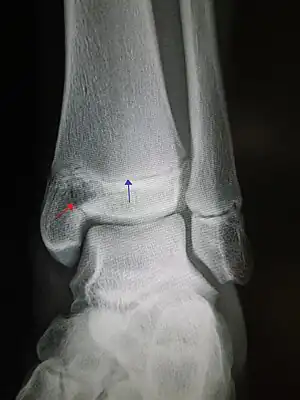

| Pott's fracture[5] | Percival Pott | bimalleolar fracture of the ankle | eversion of ankle | Pott's fracture at Who Named It? | |

| Gosselin fracture | Leon Athanese Gosselin | V-shaped distal tibia fracture extending into the tibial plafond | Gosselin's fracture Archived 2017-09-08 at the Wayback Machine at TheFreeDictionary.com | ||